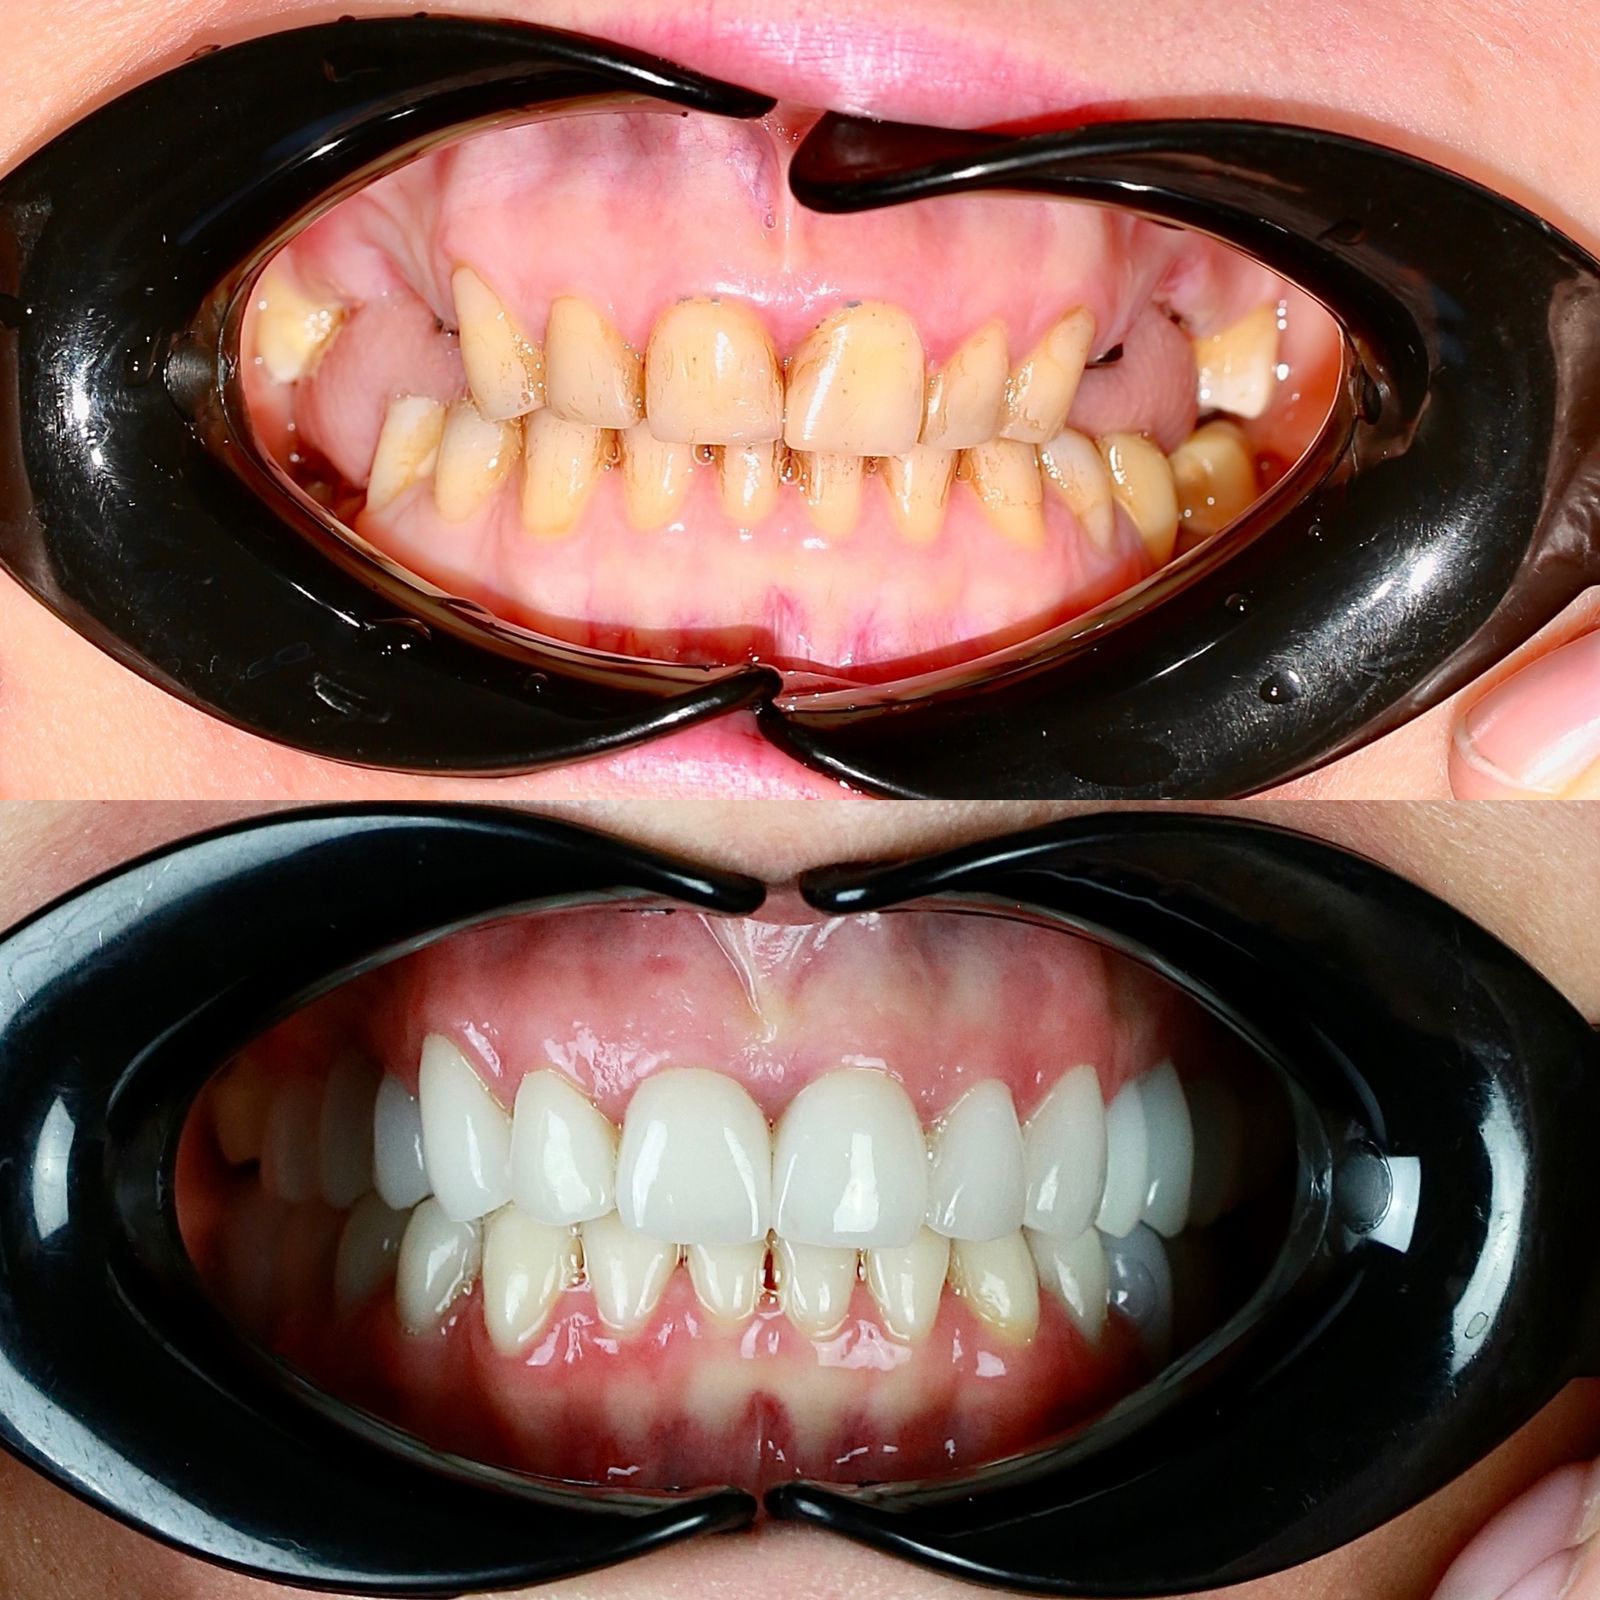

Циркониевые коронки на имплантах

На временных коронка проверена высота прикуса и окклюзия.

Установлены коронки из оксида циркония с опорой на импланты и керамические виниры на нижних фронтальных зубах.